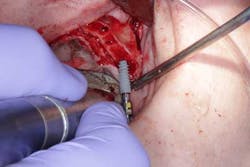

Surgery commenced. Implants on the lower arch were placed first (figures 7 and 8) and then we switched to the maxillary. The teeth were removed (figures 9 and 10) and the ridge was evened out (figures 11-13). The implants were aligned with the denture (figure 14) and then placed accordingly (figures 15-17). Healing caps were put on, and we were ready to start the restorative phase (figures 18-19).

The maxillary arch was indexed first as there was support from the palate to reference position (anterior/posterior) (figure 20). Then the lower was put into position to gain proper vertical dimension and occlusion. It, too, was then indexed; both upper and lower were given to the lab technician to start the conversion process. Next, impression copings were placed (one arch at a time) and secured with paperclips; a full-arch PVS impression was taken and likewise sent to the lab (figures 21-23). Finally, after the conversion process was completed, the bridges were secured in place on the multiunit abutments, torqued to 15nCm, and covered. Bite was adjusted and follow-up care was arranged (figures 24-26).